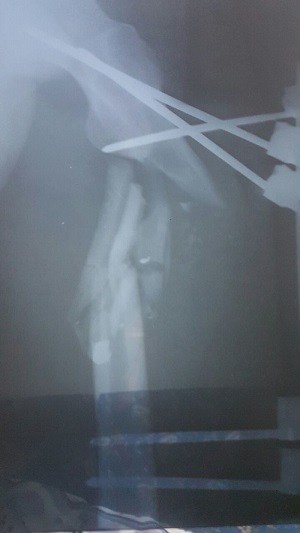

At the hospital, they X-rayed my leg, and then took me to the operating theatre. The blast had dislocated my leg and shattered my thighbone into lots of pieces. I asked if they would need to amputate, but the doctor said no.

A friend sent my X-rays to an orthopaedic surgeon he knew outside east Aleppo. He came back with bad news: the operation had been unsuccessful and I needed to be operated on all over again. The chance of them being able to do it here was minuscule. What I needed, he said, was specialist surgery across the border in Turkey.